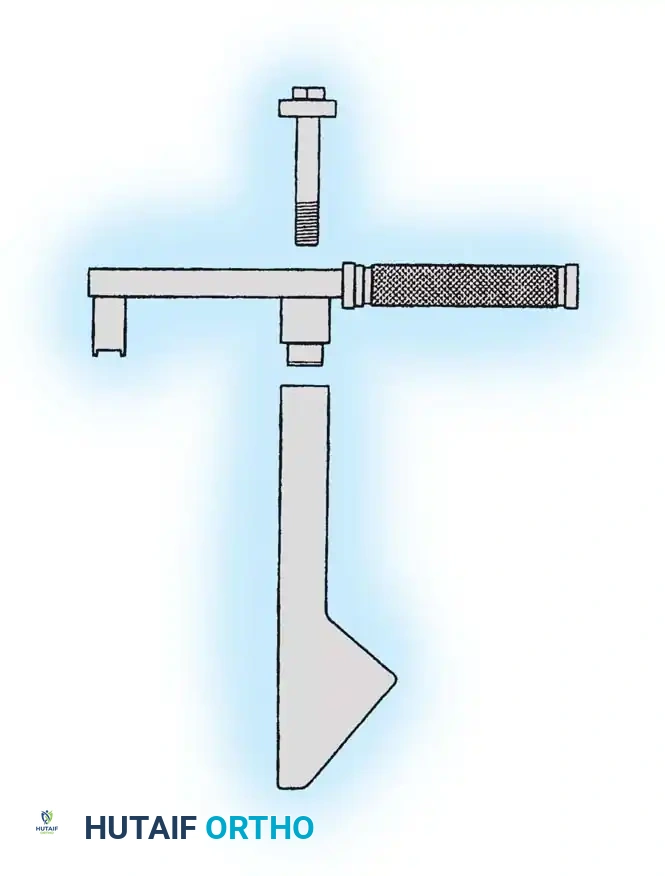

Implant Selection: SHS vs. Cephalomedullary Nail

- Sliding Hip Screw (SHS): The gold standard for stable intertrochanteric fractures (Evans Type I, AO 31-A1). The SHS allows controlled dynamic collapse along the axis of the femoral neck, compressing the fracture site and promoting primary bone healing.

3. Guide Wire Placement

Whether using an SHS or a CMN, accurate placement of the guide wire into the femoral head is the most critical step of the operation.

Insertion of the guide wire. The wire must be positioned centrally in the femoral head on both AP and lateral views.